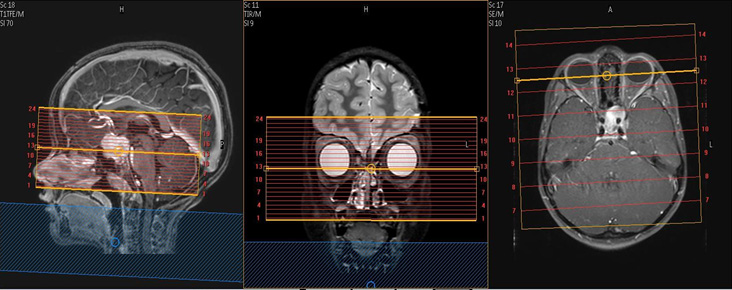

Coronal orbits coverage: Anterior margin of globe to anterior surface of pons, perpendicular to axis of the orbital segment of the optic nerves.

Axial orbits coverage: Superior margin of orbital rim to inferior margin of orbital rim, angled to be in-plane with the orbital segments of the optic nerves.

| AXIAL | DWI | 2D TSE or RESOLVE | 2 | 0.2 | YES | 17 | no | Small FOV centered on orbits. TSE or RESOLVE to avoid warp (avoid conventional EPI). Send only B1000 & ADC. Axial coverage details above. |

| AXIAL | T2 | 2D TSE | 2 | 0.25 | Dixon: InPhase & Water only | 17 | no | Orbits only. Axial coverage details above. |

| COR | STIR | 2D STIR | 2 | 0.25 | STIR | 17 | no | Orbits only. Coronal coverage details above. |

| COR | T1 | 2D TSE | 2 | 0.25 | Dixon: InPhase & Water only | 17 | no | Orbits only. Coronal coverage details above. |